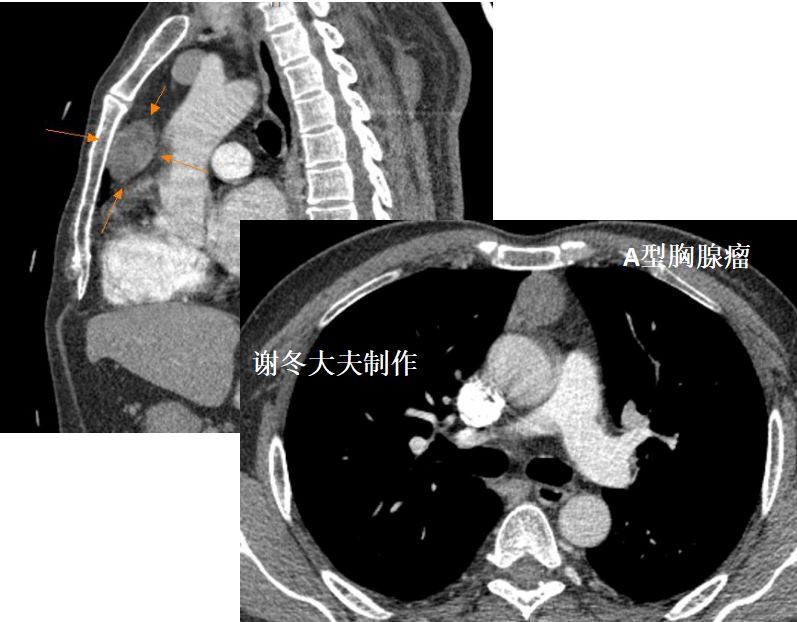

我的66例胸腺瘤,大多数是偏侧生长的, 大小也常常为大家所忽略

大部分肿瘤生长不对称,居于前纵隔的一侧; 直径 2cm的胸腺瘤可仅表现